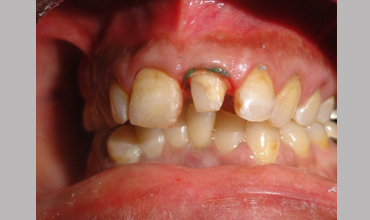

Management Of Fractured Central Incisor With Biological Post